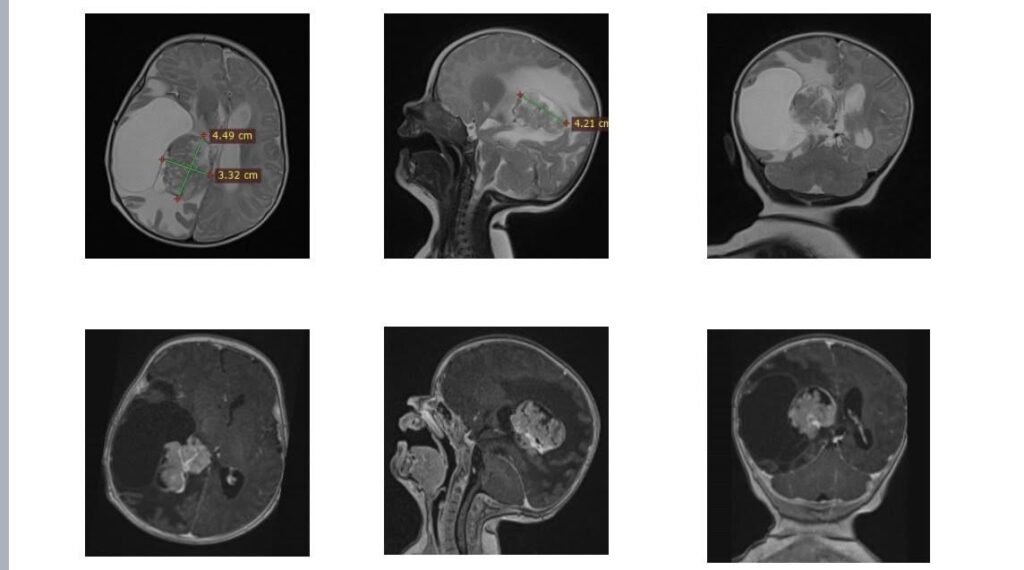

Як розповів керівник Клініки дитячої нейрохірургії Михайло Ловга, втручання було пов’язане з високими ризиками. На момент операції Олівія важила близько шести кілограмів, а пухлина знаходилася в зоні судинного сплетення з інтенсивним кровопостачанням та поблизу ділянки мозку, що відповідає за рухи. Це значно ускладнювало роботу хірургів і вимагало максимальної точності.